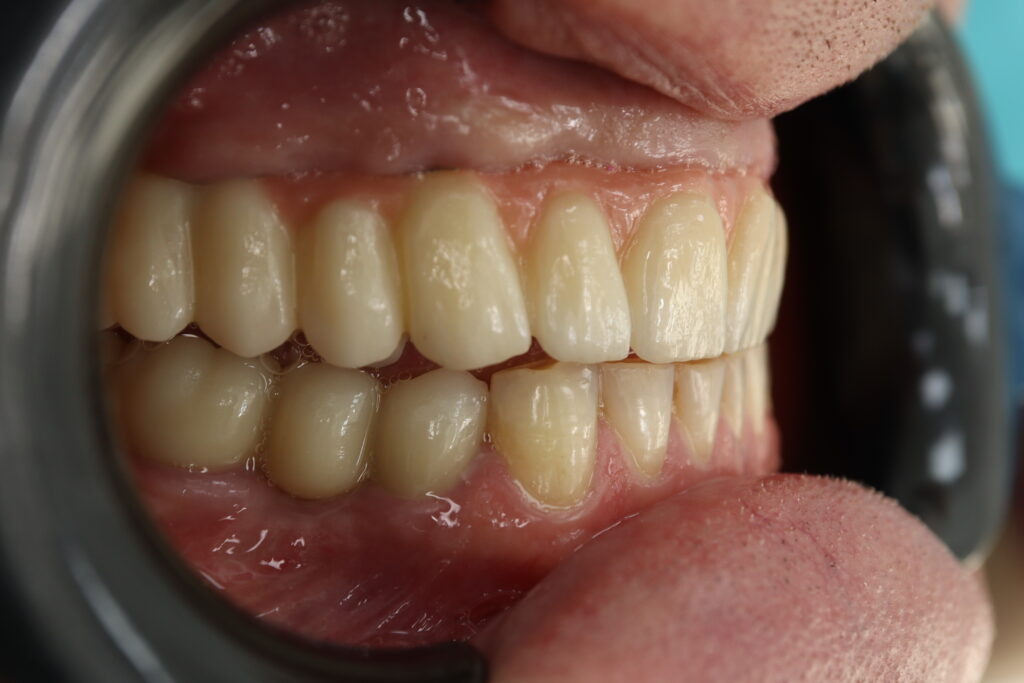

Спустя 27 дней был зафиксирован протез с опопрой на дентальные имплантаты из диоксида циркония с каркасом из титана.

Также на нижнюю челюсть был изготовлен мостовидный протез из 4х коронок (цирконий) с опорой на 3 индивидуальных абатмента с одной стороны и 1 коронка на иплантат с другой.

Пациенту были установлены 6 имплантатов Megagen AnyOne по системе All-on-6 на верхней челюсти и 4 имплантата на нижней по классической двухэтапной методике.